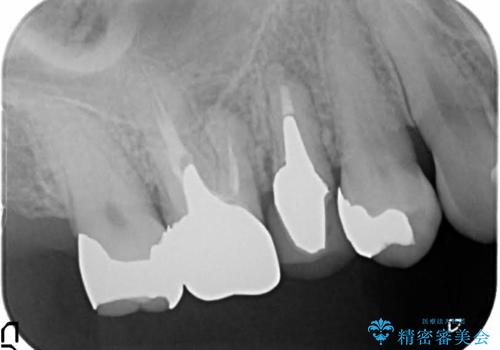

- 歯周外科による歯肉・歯の相対的な位置関係の改善

→治癒待ちの間に再根管治療、ファイバーコアの築造

根管治療や歯周外科などは、患者さんのモチベーションにあまり寄与しない反面非常に重要度が高い。これをいかに理解していただいて、労力を割くかどうかで、今後の歯のもちに大きな違いがあるといえる。

- 根管治療により痛みや腫れがひかない事や、術後に痛みや腫れが生じる事、治療によるファイル破折やパーフォレーションなどの偶発症、術後の歯根破折を生じる可能性もあります